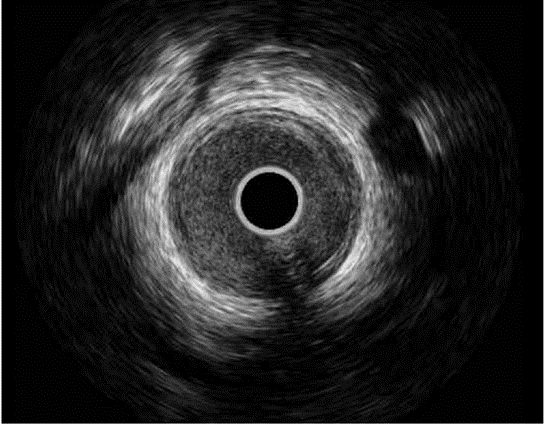

图4:术后IVUS

鉴于LAD原发病变仍存在显著狭窄,随后于病变部位再次植入1枚相同规格的药物洗脱支架。术后IVUS证实支架贴壁良好、扩张充分(图4)。整个异物取出及补救介入过程中,患者生命体征始终保持稳定。